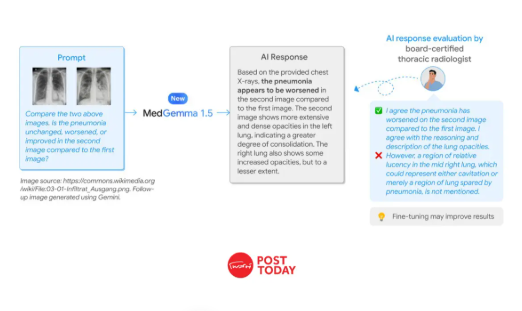

MedGemma 1.5 โมเดล AI อ่าน MRI และ CT จาก Google เปิดให้ใช้ฟรีแล้ว

Google อัปเดต MedGemma 1.5 AI การแพทย์ อ่านภาพ 3 มิติได้ทั้ง CT, MRI และชิ้นเนื้อ ช่วยแพทย์วิเคราะห์โรคแม่นยำขึ้น ใช้งานออฟไลน์ได้อย่างปลอดภัย